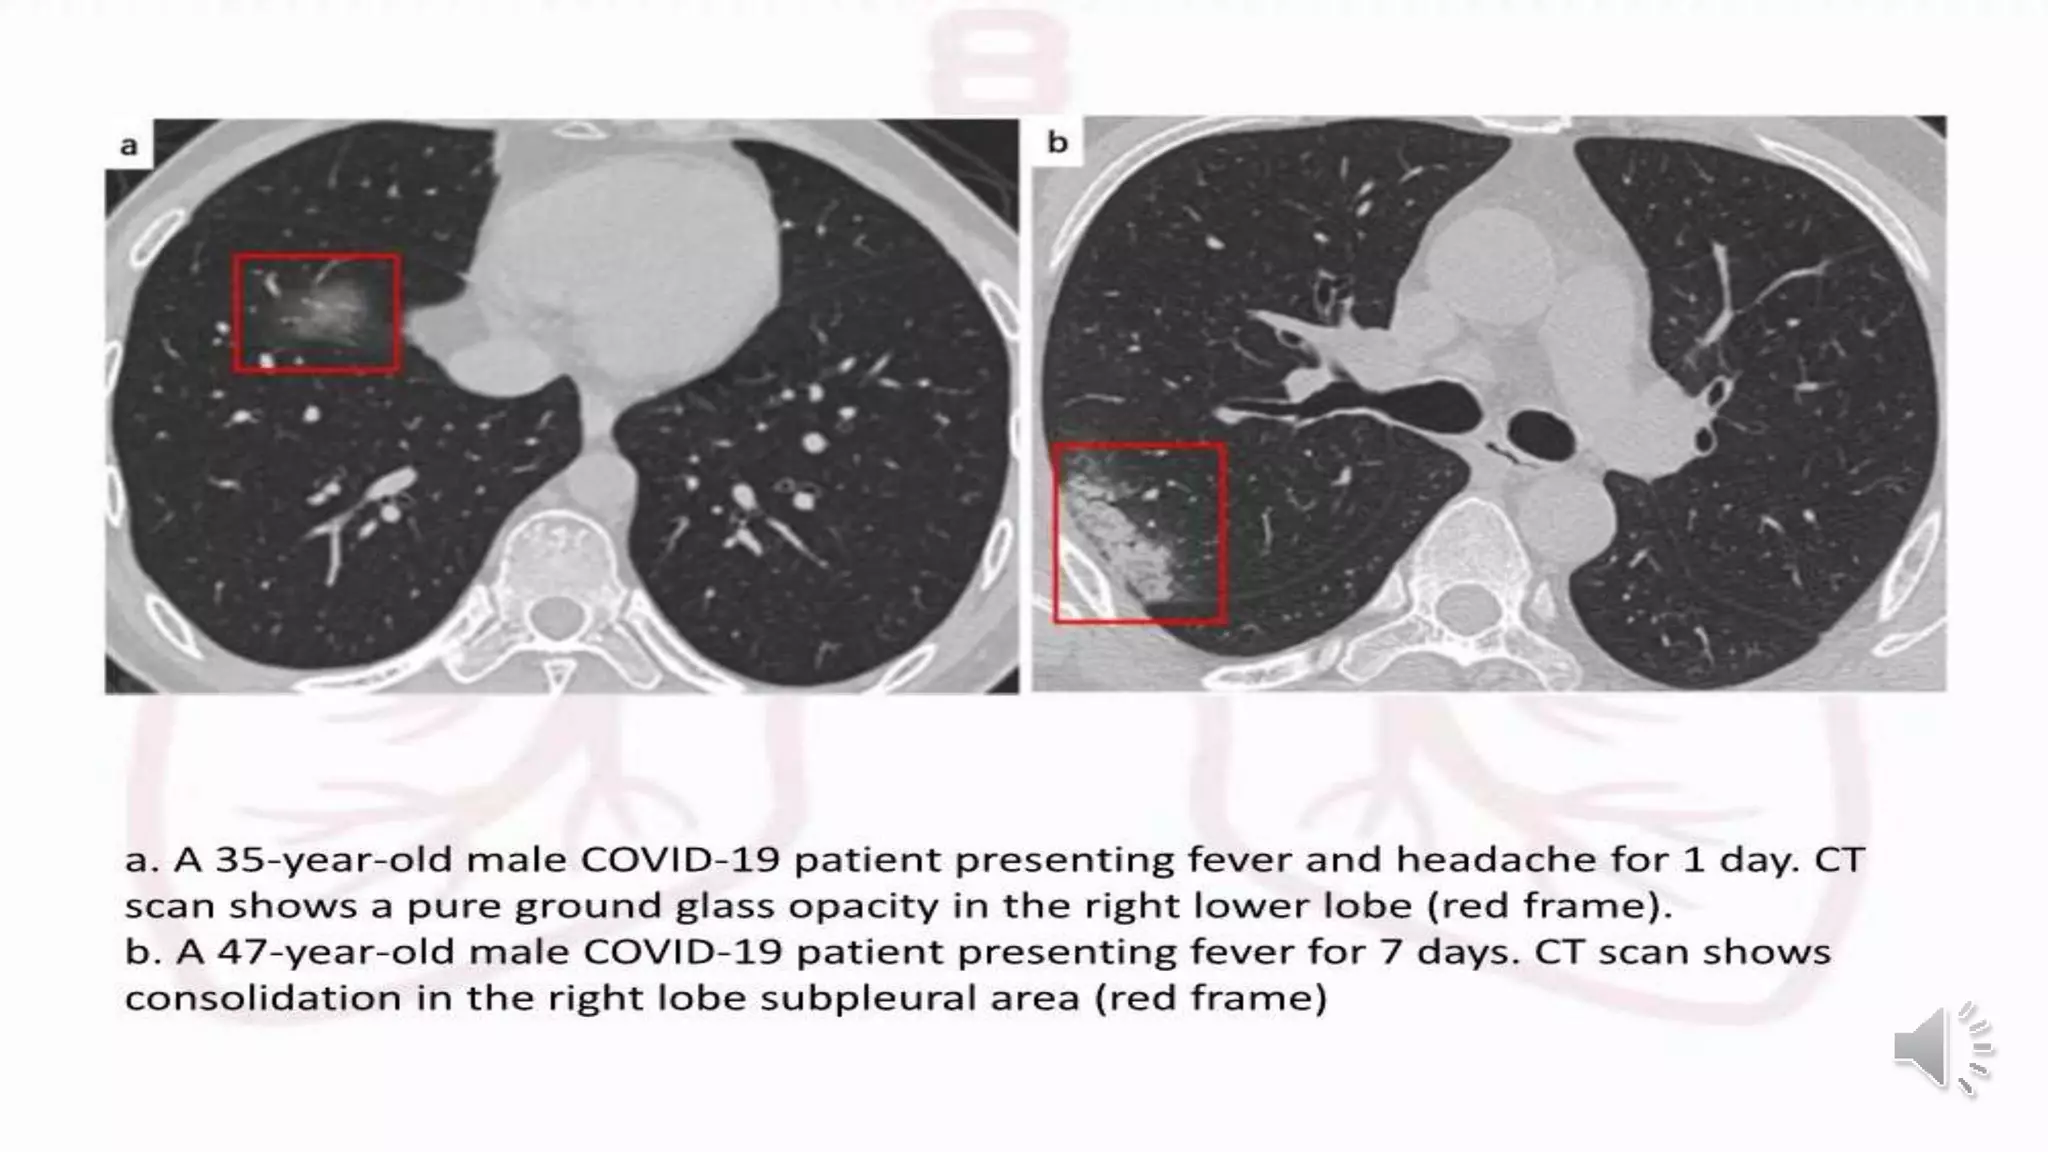

Ground glass

Ground glass (GGO) pattern is the most

common finding in COVID-19 infections.

They are usually multifocal, bilateral and

peripheral, but in the early phase of the

disease the GGO may present as a unifocal

lesion, most commonly located in the

inferior lobe of the right lung

Initial CT-findings in COVID-19 cases include bilateral,

multilobar ground glass opacification (GGO) with a peripheral

or posterior distribution, mainly in the lower lobes and less

frequently in the middle lobe .

Consolidation superimposed on GGO as the initial imaging

presentation is found in a smaller number of cases, mainly in

the elderly population.